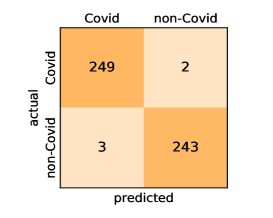

Here, we present and discuss the obtained results for detecting COVID-19 on the considered CT image datasets with different deep networks. We report the quantitative results along with the confusion matrices for every single architecture of the adopted networks.

On the SARS-CoV-2 CT dataset, ResNet101 achieves the best overall performance with respect to almost all evaluation metrics, with an average accuracy and F1-score of and , respectively. The model also achieves an average sensitivity rate of indicating that, on average, only two COVID-19 images are falsely predicted as negatives. It is also powerful enough to correctly identify all Non-COVID-19 cases with only one false positive resulting a specificity rate of . The highest sensitivity score of is achieved by the InceptionV3 model, where only one COVID-19 image is falsely predicted as negative on average. The SqueezeNet model obtains the lowest performance with respect to all evaluation metrics with a fairly acceptable average accuracy and sensitivity scores of and , respectively. Also the ShuffleNet architecture obtains satisfactory performance with approximately improvements on average for all metrics compared with SqueezeNet. Although the results obtained by these models are inferior compared with the rest of models, but they are more efficient. This matches their main objective of reducing the computational costs rather than improving their visual recognition abilities. The rest of models achieve competitive performance and very promising results with slight performance differences. Comparing the different variants of ResNet and DenseNet, we can see that the deeper variants from each architecture yield a slightly better performance. The deeper ResNet101 and ResNeXt101 show a marginal gain in performance compared with their shallower counterparts. The details about class-wise results for each model are summarized in the confusion matrices in Figure 9.

It is worthy mentioning that on the SARS-CoV-2 CT dataset the inter-fold variations are minimal and usually below one percent, showing the robustness of our fine-tuning strategy. For some of the architectures like the DenseNet variants we observe a larger confidence interval than their actual differences in recognition performance. This means that the DenseNets and the deeper ResNet variants share a very similar performance and are almost indistinguishable from each other. Overall, the obtained results by our models are better than the recently published ones even when using the same network architectures. We attribute this to the better optimization and transferability of the learned features when applying our fine-tuning strategy.